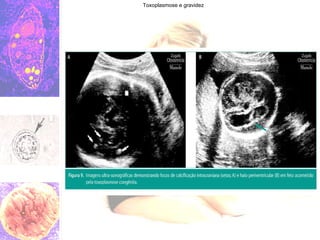

Toxoplasmose e gravidez Investigação do comprometimento fetal USG morfológica do 1 e 3 trim Microcefalia ou hidrocefalia,  Hidropsia Hepatoesplenomegalia Placentomegalia Oligo ou polidrâmnio Ecocardiograma fetal após 20 sem Anomalias cardíacas

Toxoplasmose e gravidez Diagnostico da infecção no período neonatal Quadro clinico variado e inespecífico: Microcefalia, hidrocefalia,convulsão Coriorretinite, catarata, glaucoma, microftalmia Hepatomegalia, esplenomegalia Anemia, púrpura, hidropsia USG e TC de crânio Calcificações intra-cranianas Laboratorial(sangue periférico do RN) IgG: AC maternos passam da mãe para o feto IgM, IgA ou PCR: especificidade e sensibilidade - confirma o diagnostico